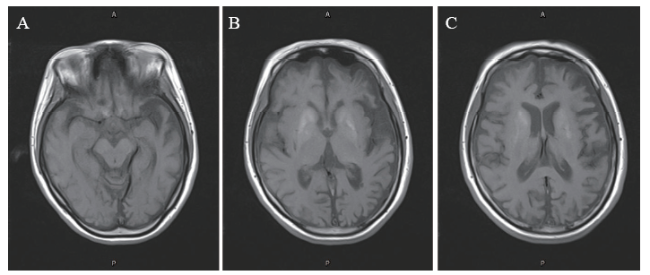

例3 患者女,24岁,因反复头痛、抽搐11年,再发抽搐2 d于2018年12月17日入中山大学附属第一医院。患者于11年前无明显诱因出现发热,体温38 ~ 39℃,并伴较为剧烈的头痛,呕吐胃内容物数次,无不省人事、二便失禁,在当地医院治疗后发热好转,但偶有烦躁及右侧肢体抽搐,右侧肢体无力,智力下降,其后转来中山大学附属第一医院,诊断为病毒性脑炎,继发性癫痫,予激素、抗病毒、抗癫痫等治疗后,症状好转,出院后口服泼尼松、丙戊酸钠治疗,仍有反复头痛、抽搐、左侧或右侧肢体麻木与无力,智能逐渐下降,生活基本能自理,多次入院治疗,2011年5月患者再次出现右侧肢体无力、抽搐而入院,行基因检测确诊为线粒体脑肌病、症状性癫痫,予改善脑部能量代谢,托吡酯片、利必通抗癫痫治疗,症状好转后带药出院,偶有抽搐发作,自行调整托吡酯片用量后抽搐能控制,生活基本能自理,能参加工作。2013年相同症状再发,入院经相同治疗后好转出院。2015年6月20日患者在洗澡过程中突发四肢无力,站立不稳,并伴头晕、低热(体温不详),2015年6月21日反复出现右侧上肢抽搐、乱语、神志不清,再次入院,患者及其母亲接受基因检测示MELAS相关的杂合性突变m.3243A > G,患者经对症治疗后好转出院。2015年7月14日及2016年9月6日患者均因反应迟缓、答非所问再次入院治疗,曾行MRI检查,2015年8月3日脑血管磁共振血管成像(MRA)示:①双侧基底节核团异常信号影;②双侧壳核异常信号影;③双侧额叶、双侧颞叶、枕叶、岛叶皮层弥漫性异常信号,以右侧颞叶显著;④脑萎缩; ⑤脑血管未见明确异常。患者出院后坚持服用托吡酯片、复合维生素B、艾地苯醌片(金博瑞)、三磷酸腺苷、辅酶Q10、奥拉西坦等治疗,未再发肢体抽搐。本次入院前2 d患者无明显诱因出现抽搐,表现为四肢抽动,肢体抽动时神志不清,呼之不应,半小时左右发作1次,每次持续数十秒,发作频繁,每次发作症状一致,故再次入院治疗。起病以来患者精神、食欲、睡眠差,二便正常;平素健康状况一般,既往史、个人史等无特殊;父母健在,其母有类似病史,被诊断为“线粒体脑肌病”,否认其他家族遗传病、传染病或精神病史。入院时体格检查:体温36.5℃,脉搏98次/分,呼吸15次/分,血压102/71 mm Hg,神志清晰,无幻觉、妄想,理解力为部分理解,言语流利,反应迟缓,答非所问,查体不合作。时间、地点、人物定向力异常,近、远事物记忆力及计算力减退,阅读、书写能力、失认检查不合作。视力检查不合作,双侧面部痛、触觉检查不合作,刺激右下肢不能于床面移动,左下肢可抬离床面,右下肢肌力4级,左下肢肌力5-级,肌张力不高,双侧病理征阴性,脑膜刺激征阴性。血乳酸8 mmol/L(参考值0.9 ~ 2.3 mmol/L)。肌电图示肌源性损害。颅脑MRI检查与2015年8月检查时对比:①双侧基底节区异常信号范围与前相仿;小脑见新发异常信号灶;双侧大脑半球异常信号灶部分新发,部分较前相仿,部分消失,左侧额叶后上部中线旁见条状弥散受限区;②脑萎缩较前加重(图1)。予患者营养神经,抗癫痫等对症支持治疗,症状好转后出院。出院诊断:①线粒体脑肌病(MELAS);②症状性癫痫。

图1 一例MELAS患者颅脑MRI图